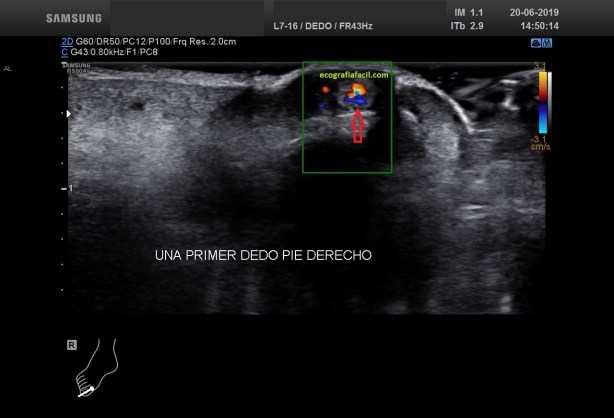

Habrás observado que estamos ante una lesión treméndamente vascularizada, en el enlace que te puse al principio del post habla del tumor glómico como una tumoración vascular y benigna. Ahí tienes la explicación y el diagnóstico de dicha lesión. En la fig 6 puedes observar que el doppler pulsado capta un claro espectro arterial.

You will have observed that we are facing a tremendously vascularized lesion, in the link that I put at the beginning of the post speaks of the glomic tumor as a benign vascular tumor. There you have the explanation and diagnosis of this injury. In fig 6 you can see that the pulsed doppler captures a clear arterial spectrum.